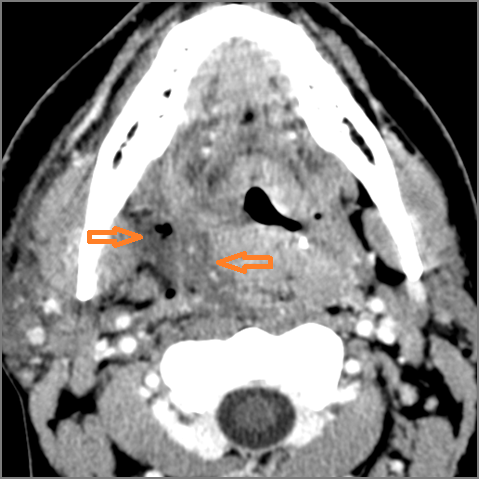

Oropharynx

There is excessive enhancement or thickening of the mucosa or hypertrophy of the palatine or lingual tonsillar tissue or the lymphoid tissue along the glossotonsillar sulci and posterior pharyngeal wall. [Yes/No]

There is abscess relatively centrally within the lymphoid tissue of the palatine tonsil. [Yes/No]

There is abscess at the periphery of the lymphoid tissue of the palatine tonsil within the potential peritonsillar space of the palatine tonsil within the potential peritonsillar space [Yes/No]

There is edema/abscess within the fat of the adjacent parapharyngeal and retropharyngeal spaces. [Yes/No]